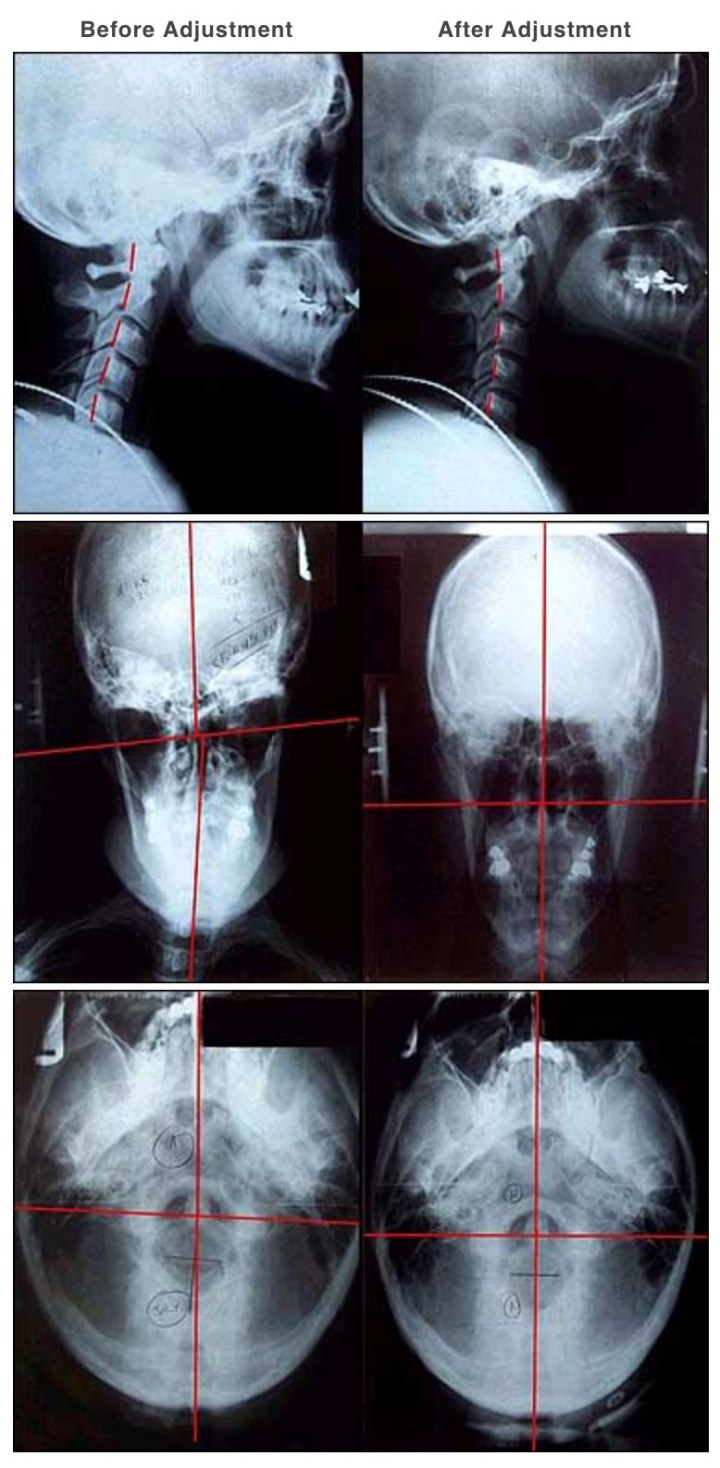

This series of xrays shows how a NUCCA adjustment brings the neck into alignment. You can see in the first X-ray, the head is slightly forward, in the second, the head is aligned over the neck (as it should be).

PS: This is my X-ray before my first adjustment. The red line shows where my neck should align. I should also have more of a curve, but damaged disks have destroyed the possibility of total correction. The correction I gain after each adjustment is enough to give me a great deal relief.